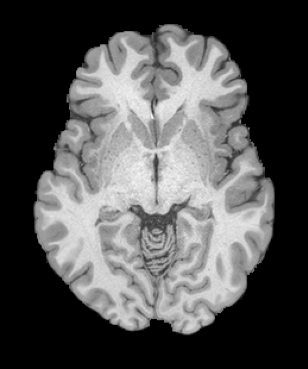

HCP Brain MRI We train on 1076 brain-extracted T1w images from the HCP dataset [24] and test on a sample of 100 pairs between 36 images via mean Dice over 28 midbrain structures [20, 21]. We train and execute the network at [130155130], then compute the Dice score at full resolution.

OASIS Brain MRI We use the OASIS-1 [12] data preprocessed by [9]. This dataset contains images of 414 subjects. Following the data split in [14], we train on 255 images and test on 153 images555Due to changes in the OASIS-1 data, our test set slightly differs from [14]. We evaluate all methods using our testing protocol so that results are consistent.The images in the dataset are of size [160192224], and we crop the center of the image according to the preprocessing in [14], leading to a size of [160144192]. During training, we sample image pairs randomly from the train set. For evaluation, we randomly pick 5 cases as the fixed images and register all the remaining 148 cases to the 5 cases, resulting in 740 image pairs overall.

| Moving Image | Warped Image | Fixed Image | Moving Image | Warped Image | Fixed Image |